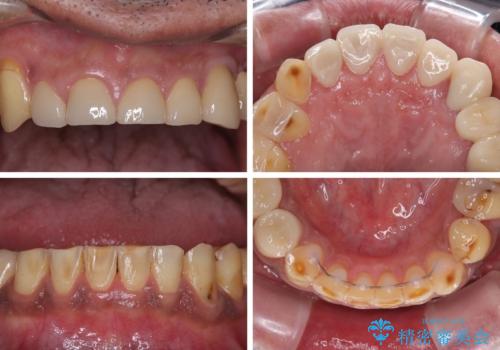

矯正治療は想定通り長期化しましたが、しっかりと奥歯の咬み合わせを向上させて前歯の被蓋を改善させることができました。

目立つ銀歯やすり減った前歯がセラミッククラウンとなり、患者様には大変満足していただけました。